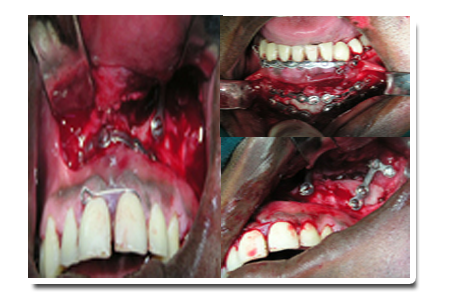

A patient with facial trauma can be corrected by plating surgery as shown below: